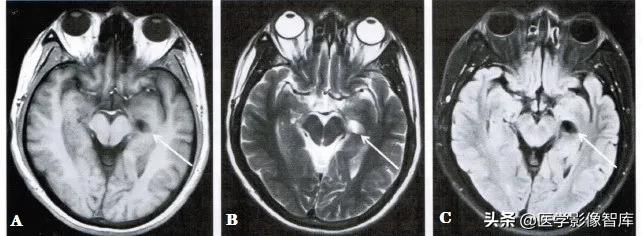

图2 左侧脉络膜裂囊肿

男性,58岁。A.轴面T1WI。B.轴面T2WI。左侧脑室颞角内侧可见一个囊状长T1、长T2信号影(箭);C.轴面T2 FLAIR,囊肿在脑脊液抑制像上呈低信号(箭)。

因此,脉络膜裂囊肿常沿脉络膜裂和海马沟成角,呈现一个箭头样改变或表现为颞叶内侧的卵圆形、纺锤形囊肿。囊肿长轴沿后上至前下斜行为其特征。在T1WI、T2WI, T2 FIAIR及DWI上,脉络膜裂囊肿的MR信号强度与脑脊液的信号强度基本一致,边界锐利,病灶周围的脑实质无水肿表现(图1、图2)。注射对比剂后增强扫描时囊肿无异常强化。鉴别诊断包括颅内表皮样囊肿、囊性肿瘤、脑软化灶等。